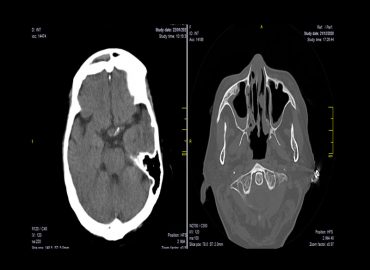

Paciente de sexo femenino 75 años MC: Ptosis palpebral derecha y parálisis ocular homolateral